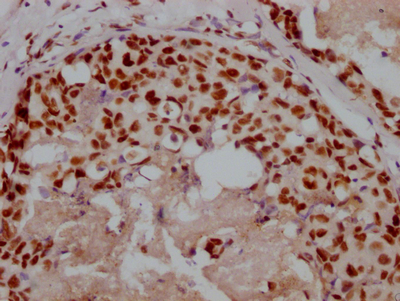

IHC image of CSB-RA169000A0HU diluted at 1:100 and staining in paraffin-embedded human liver cancer performed on a Leica BondTM system. After dewaxing and hydration, antigen retrieval was mediated by high pressure in a citrate buffer (pH 6.0). Section was blocked with 10% normal goat serum 30min at RT. Then primary antibody (1% BSA) was incubated at 4°C overnight. The primary is detected by a Goat anti-rabbit polymer IgG labeled by HRP and visualized using 0.05% DAB.